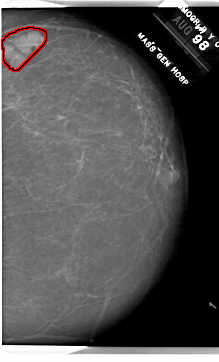

A_1843_1.RIGHT_MLO

RIGHT_MLO LINES 6721 PIXELS_PER_LINE 5206 BITS_PER_PIXEL 12 RESOLUTION 43.5 OVERLAY

FILE: A_1843_1.RIGHT_MLO.OVERLAY

TOTAL_ABNORMALITIES 1

ABNORMALITY 1

LESION_TYPE MASS SHAPE LOBULATED MARGINS CIRCUMSCRIBED

ASSESSMENT 2

SUBTLETY 5

PATHOLOGY BENIGN

TOTAL_OUTLINES 1

BOUNDARY